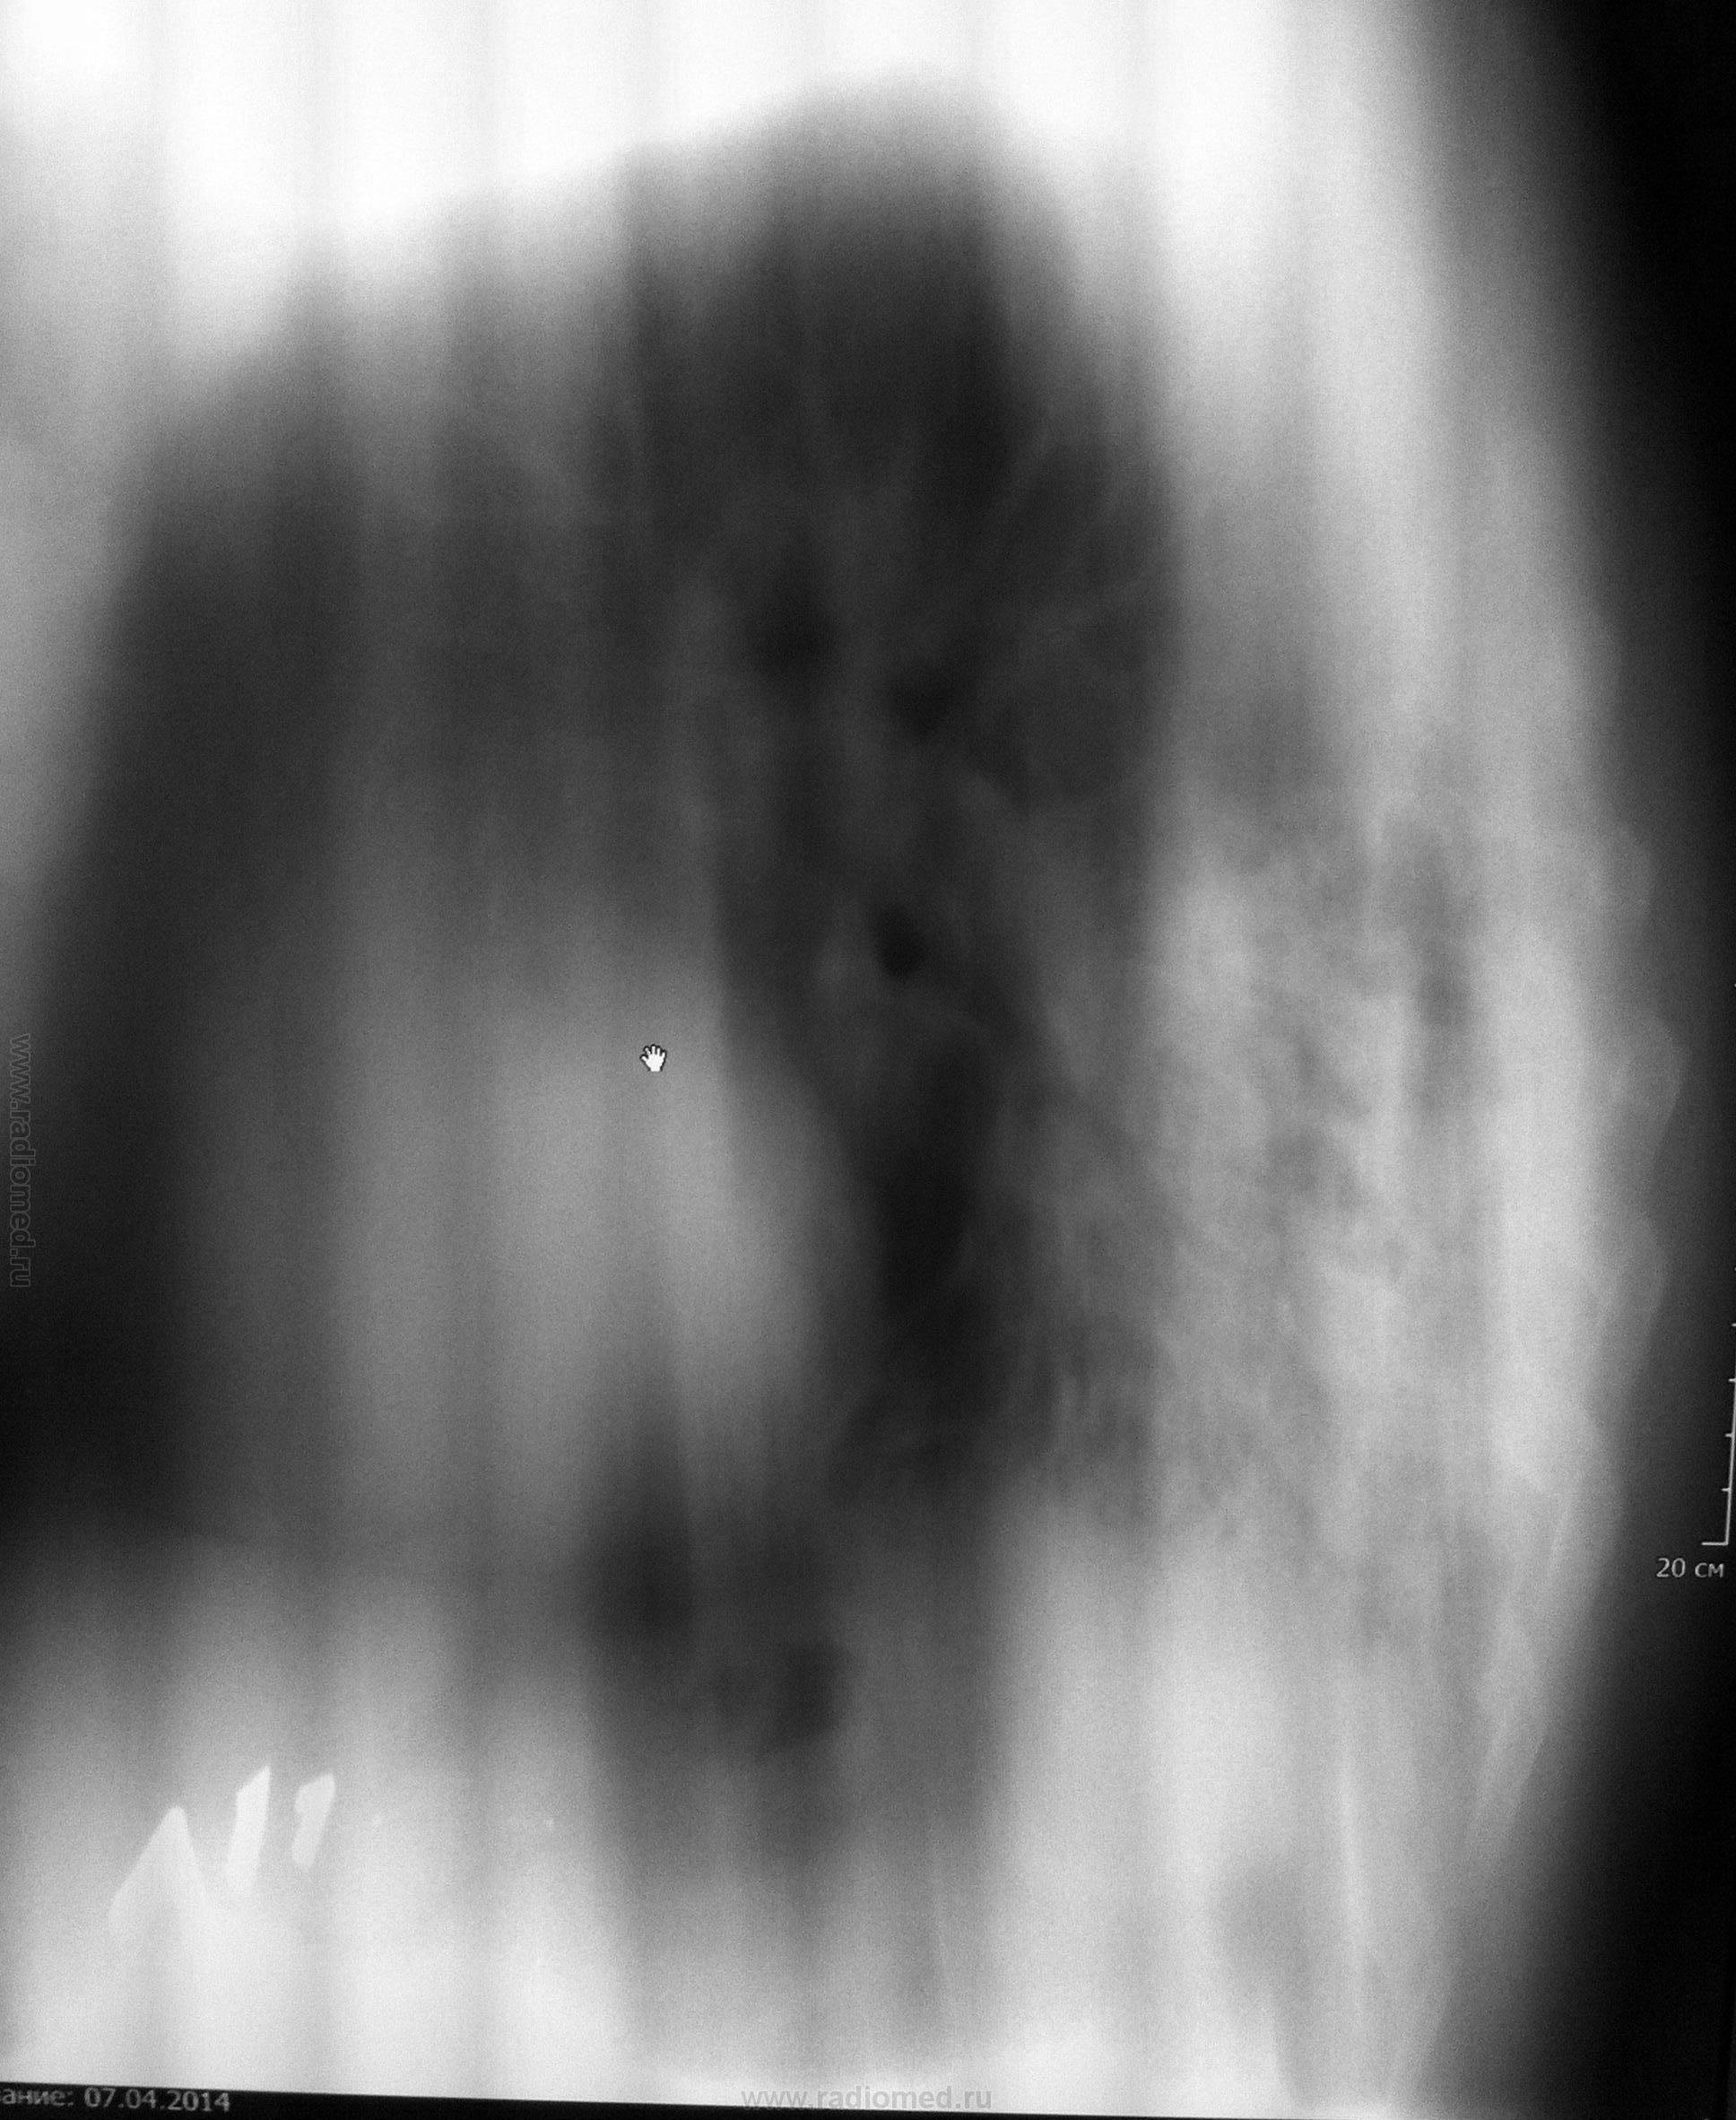

Прошу прощения, не поняла, как повернуть фото. Первые 3 снимка 31.03.2014г. Затем контроль 7.04.2014г., томограммы в этот же день на предмет исключения центрального рака.

конечно, смотреть сложно в повернутом виде, поэтому можно только предположить, но я согласна с Вами, что здесь нельзя исключить центральный с-ч, даже при наличии отрицательных данных ФБС - широкий левый корень, расширенное верхнее средостение и гиповентиляция в нижней доле слева. Поэтому, рекомендую КТ и консультацию онколога повторно.

Присоединяюсь-цикличность левого корня и гиповентиляция верхнего сегмента нижней доли.КТ поставит точку

Динамика отрицательная.Впечатление о нижнедолевой пневмонии слева, осложнённой гиповентиляцией. Так что и рак - не исключён, с параканкрозным пневмонитом

Опухоль нужно искать, нижняя доля слева в гиповентияции, средостение влево уезжает, это не пневмония

Уважаемые коллеги, спасибо за помощь! С 31.03. по 7.04. Лечили аугментином, амброксолом, сальбутамолом и т.д. Клинически больному не хуже, пришел на контроль перед выпиской. Рекомендовала КТ для исключения центрального преимущественно эндобронхиального рака нижней доли левого легкого, осложненного гиповентиляцией S6,10. КТ сделали, заключение: пневмония в нижней доле левого легкого, ст. разрешения. Бронхоэктазы. Пуль монологи довольны, больной выписан.

КТ нужно было делать до ФБС. А после нее они получили картину кровоизлияний и расценили как пневмонию. Это -мое предположение, но то, что уже "кровило" во время проведения ФБС, -еще один аргумент за "зло".В заключении бронхоскопии об этом должно быть написано.Так что -прямая дорога к онкологам и вы правы, что заподозрили рак.